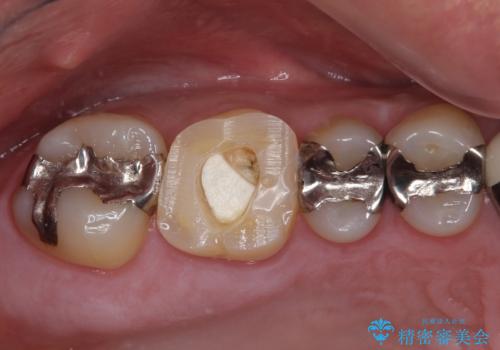

- 上下前歯のデコボコと下顎小臼歯の欠損によるスペースを気にして来院された患者様です。

下顎は左右1本ずつ小臼歯が欠損しており、右側にはやや大きな欠損がありました。

咬合力が強く、インビザラインのみではディープバイトを改善することができず、半年間ほどワイヤー装置による矯正治療を行いました。